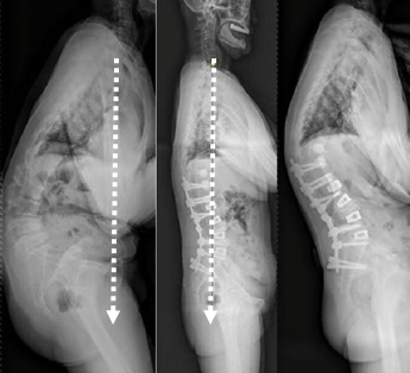

图23 选择合适的UIV

1.选择合适的UIV

(1)固定近端交界性后凸角>5°的区域应包括在融合区内;

(2)胸椎后凸过大患者,融合水平应跨过胸椎后凸节段到上胸段;

(3)尽量跨过交界区,如胸腰段尽量不终止于T11和T12;

(4)颈7铅垂线距离UIV不要太远;

(5)矢状面上UIV上方椎间隙无后凸角度。